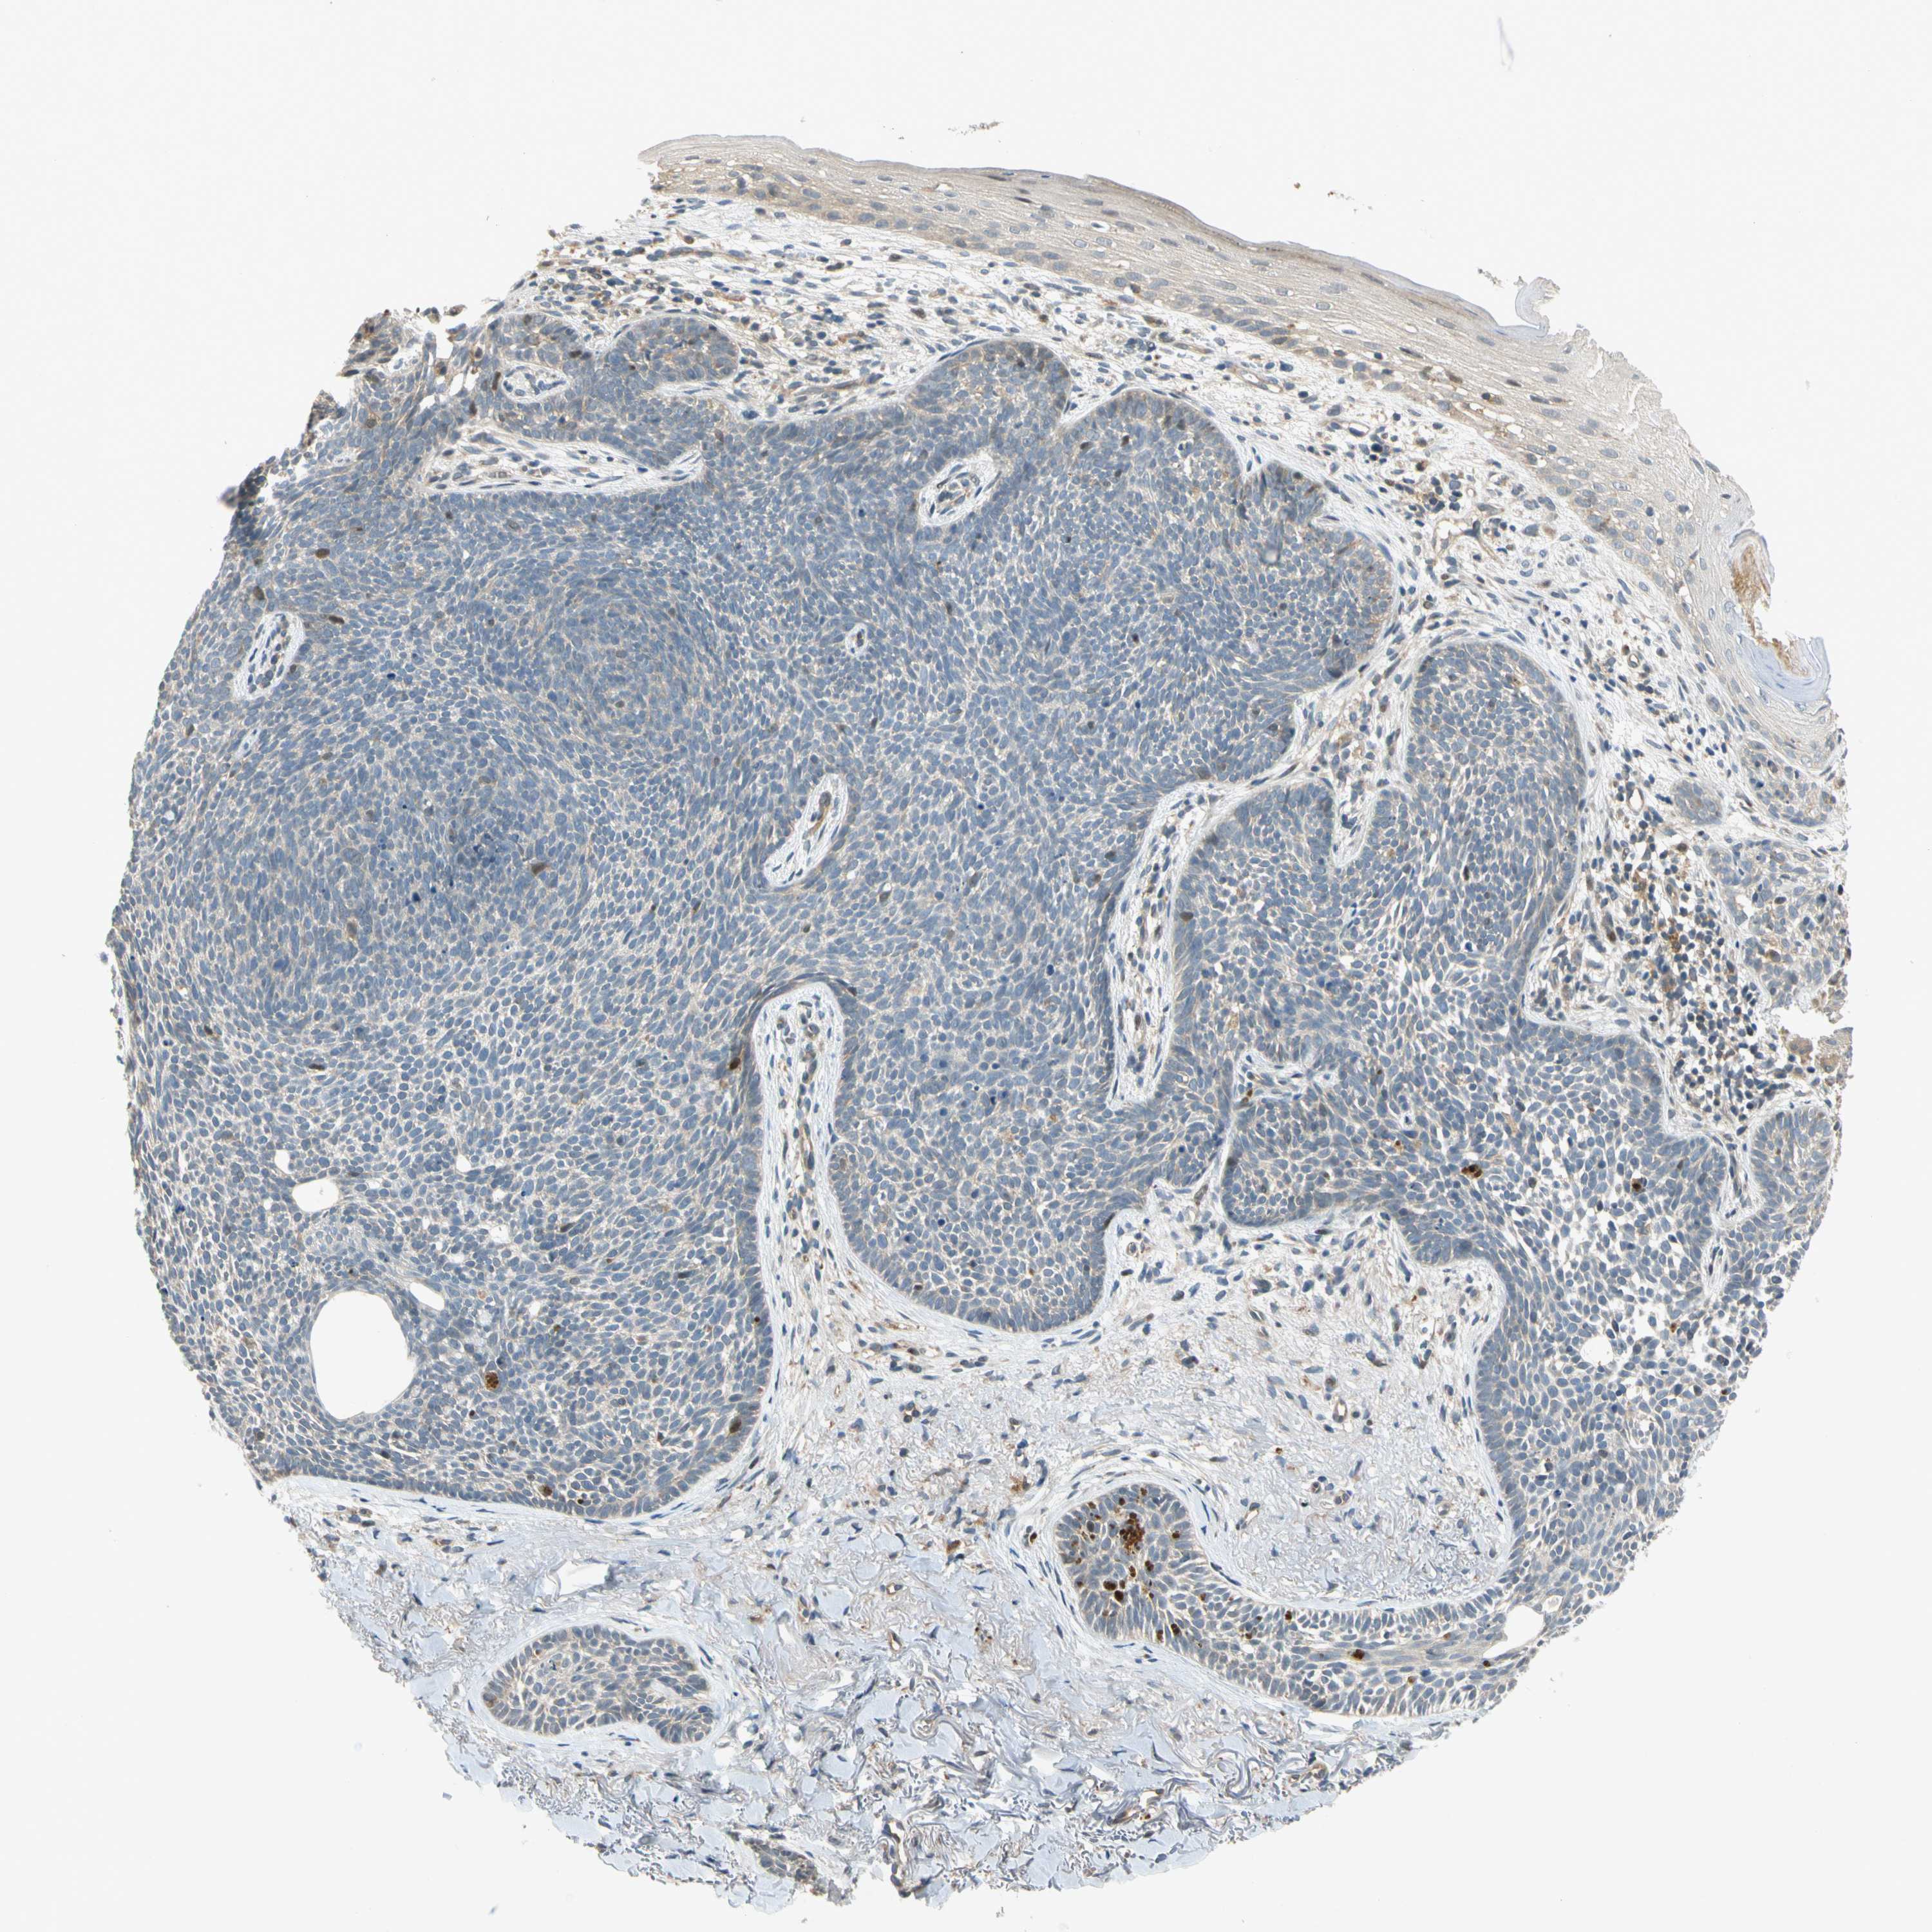

CANCER SKIN CANCER Show tissue menu

Basal cell and squamous cell cancer

SKIN CANCER - Protein expressioni

A mouse-over function shows sample information and annotation data. Click on an image to view it in a full screen mode. Samples can be filtered based on level of antibody staining by selecting one or several of the following categories: high, medium, low and not detected. The assay and annotation is described here.

Each image is clickable and will lead to virtual microscopy that enables deeper exploration of all samples and also displays staining intensity scores, fraction scores and subcellular localization as well as patient and tissue information for each sample.

Antibody HPA008812

Staining

High

Medium

Low

Not detected

Intensity

Strong

Moderate

Weak

Negative

Quantity

>75%

75%-25%

<25%

None

Location

Nuclear

Cytoplasmic/membranous

Cytoplasmic/membranous,nuclear

Squamous cell carcinoma, NOS

Basal cell carcinoma